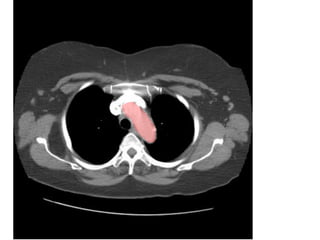

Giải phẩu CT ngực – các mạch máu

lớn.

SVC: tĩnh mạch chủ trên.

Aortic arch: cung đm chủ

Pulmonary artery: đm phổi

Main sterm bronchus: phế quản gốc